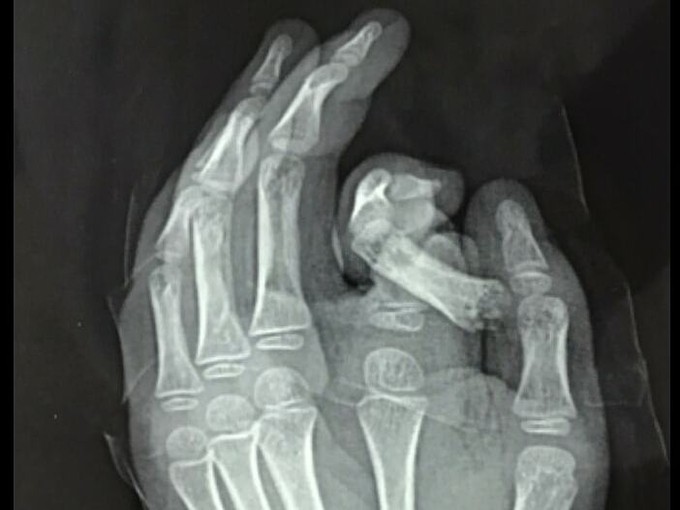

HÀ NỘI - Bé trai 6 tuổi cho tay vào máy giặt đang hoạt động, ngón trỏ đứt rời, hệ thống thần kinh dây chằng bị nhổ bật, dập nát.

Bé được đưa vào cấp cứu tại Bệnh viện Đa khoa Xanh Pôn, ngày 17/12. Các bác sĩ đã cố gắng bảo tồn và nối ngón tay cho bé. Tuy nhiên, tình trạng dập nát quá nặng và bệnh nhi nhỏ tuổi nên hiện tại chưa thể nối được. Các bác sĩ đang tiếp tục điều trị và lên phương án xử trí tiếp theo.

Phim chụp X-quang bàn tay bị tổn thương của trẻ. Ảnh: Bệnh viện cung cấp.